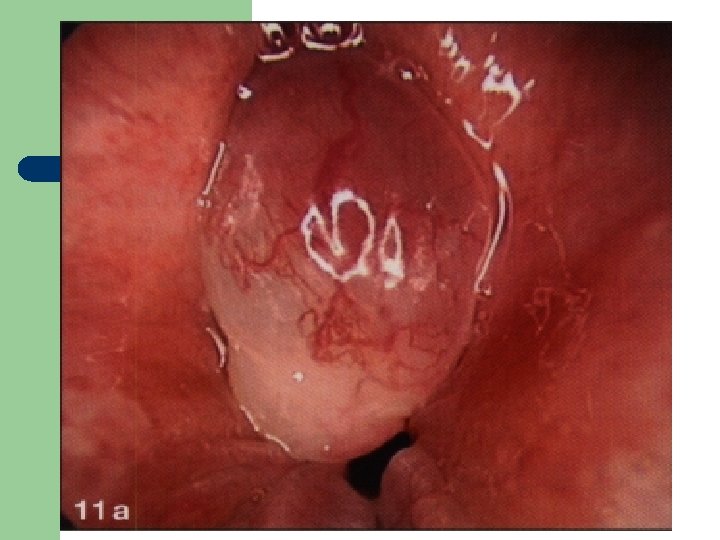

Vývoj dětské chraptivosti l 1. 2. 3. 4. Průvodním jevem při dětské chraptivosti je pokašlávání a pochrchlávání. Nález na hlasivkách postupuje takto: Hyperemické (překrvené hlasivky, Hypertrofické, vřetenovité zduření, hlasivkový uzávěr je neúplný a hlas má dyšnou příměs, ventrikulární řasy se začínají vyklenovat Zpěvácké uzlíčky, nejčastěji na hranicích přední a střední třetiny hlasivek Atrofie hlasivek až s podélnou rýhou, při fonaci nedomykavost uzávěru.

Hlasivkový uzlík l

Hlasivkový uzlík l

Hlasivkové uzlíky l